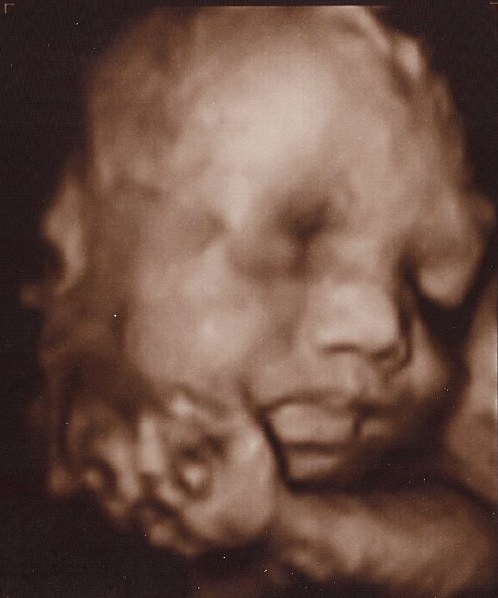

Det er så vildt at være til 3D scanning, det er som om, man er gravid på en helt anden måde bagefter

Ja, virkelig! Det er en hel anden måde at forholde sig til den lille på! Men når man ser billederne synes jeg man tænker "iih hun er stor", men hun er jo i virkeligheden stadig lillebitte. Lidt skægt